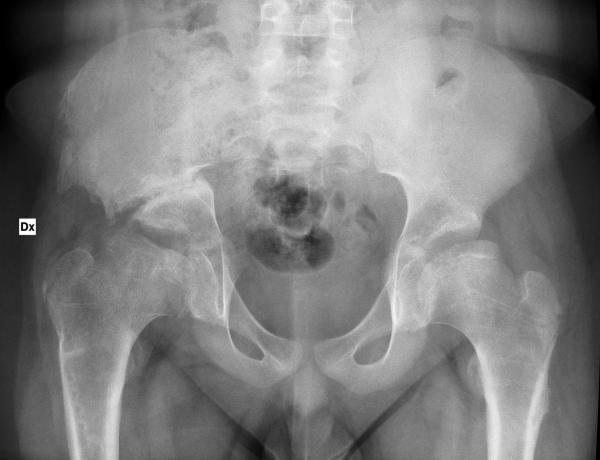

L’osteotomia di bacino secondo Chiari è una osteotomia trasversa sopra-acetabolare, nella quale il moncone craniale dell’ileo viene lateralizzato (3,12). Quale conseguenza della relativa medializzazione del blocco ischio-pube-acetabolo, si ha una sensibile riduzione del diametro trasverso del bacino. Questa situazione è ancora più evidente nei casi, non rari, di osteotomie di Chiari bilaterali. Le indicazioni a questa osteotomia di bacino in età pediatrica sono diverse, legate prevalentemente al trattamento della lussazione congenita dell’anca, con la finalità di ampliare la cavità acetabolare aumentandone la congruenza con l’epifisi femorale (4); e nel trattamento degli esiti di morbo di Perthes, con lo scopo di modificare il carico al quale l’articolazione viene sottoposta (figura 1).

La coxa protrusa rappresenta la forma più grave della malformazione dell’anca caratteristica della “coxa profunda”, più frequente (70-80% dei casi) nel sesso femminile (5). L’acetabolo si presenta bilateralmente come affondato nell’ileo, e procide in maniera anomala all’interno del bacino, portandosi medialmente alla linea innominata. Questa condizione è già evidente in tutta la sua gravità in età pediatrica, anche se asintomatica nella maggior parte dei casi, ed è presente quindi già nella giovane adulta in età fertile.